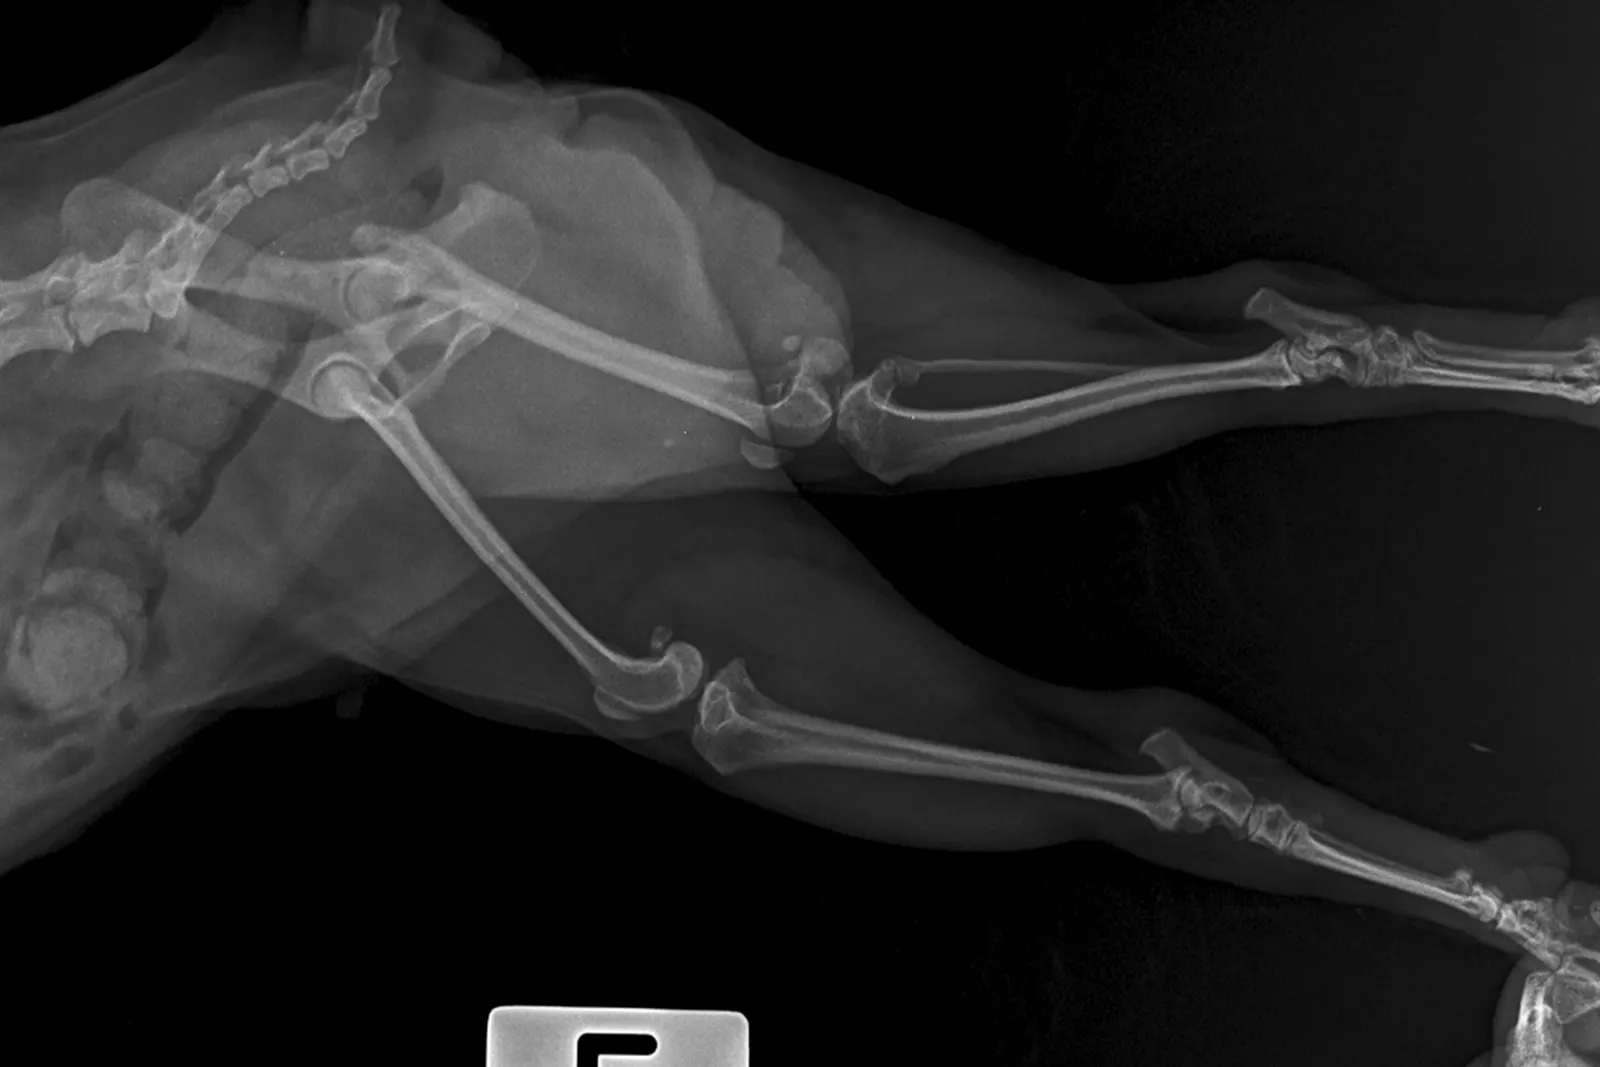

Riječ displazija znači nepravilan razvoj. Razvojna bolest lakta je možda bolji naziv, jer pri spomenu displazije, većina ljudi pomisli na displaziju kuka.

Lakat se sastoji od tri kosti, i ako one ne naliježu apsolutno savršeno (posljedica nepravilnog razvoja), dolazi do krivog rasporeda sila na određenim mjestima u zglobu lakta. Oblici primarne bolesti hrskavice također mogu dovesti do lošeg razvoja zgloba lakta, što rezultira ozbiljnim kliničkim znakovima.

Kod displazije lakta, sile koncentrirane na određenim točkama u zglobu neće samo dovesti do osteoartritisa (kao kod displazije kuka), već i do manjih patoloških promjena, kao što su prijelomi unutar zgloba, koji se moraju rješavati odvojeno ili zajedno s osteoartritisom zgloba. Termin displazija lakta koristi se kao sveobuhvatni naziv za to, jer su manifestacija iste zglobne patologije - nepravilnog razvoja zgloba. Stoga ih u praksi vidimo zajedno na istom zglobu.

Displazija lakta je najčešći uzrok šepavosti prednjih nogu u mladih pasa, velikih i divovskih pasmina. Većina pasa šepa na jednu, ali mogu šepati i na obje prednje noge. Neki psi koji šepaju na obje prednje noge neće šepati, već će imati neobičan hod.

Okidač za šepanje obično je produljeni odmor ili aktivnost.

Mnogi psi s displazijom lakta šepaju nakon spavanja, kad se zagriju prestanu te nakon duže aktivnosti ponovo šepaju.

Kod većine pasa se ova bolest dijagnosticira prije druge godine života, ali kod nekih se manifestira tek u starijoj dobi.

Displazija lakta i osteoartritis lakta najčešći su uzroci šepavosti prednjih nogu u pasa bilo koje dobi.

Stoga na displaziju lakta treba posumnjati kod svakog psa koji šepa na prednje noge, ako uzrok šepanja nije trauma.

Ova je bol u osnovi genetska, iako na nju utječu i naknadni čimbenici, poput pretilosti u štenećoj dobi.

Kod većine pasa s displazijom lakta, patologija uključuje koncentraciju abnormalnih sila na dijelu zgloba koji se naziva koronoidni nastavak ulne. Te abnormalne sile uzrokuju mikroskopske prijelome na koronoidnom procesu, a kod većine pasa se mali dio ostruge ili cijela ostruga odvoji od ostatka kosti.

Ovaj problem se naziva fragmentirani koronoidni proces (FCP) i jedan je od procesa koji spadaju u displaziju lakta.

Standardna dijagnostička procedura je RTG, ali ponekad je potrebno učiniti i CT jer daje informacije o sitnim koštanim patologijama ispod hrskavice.

Kako bi se odredio optimalni tretman za displaziju lakta, potrebno je identificirati i neutralizirati razloge.